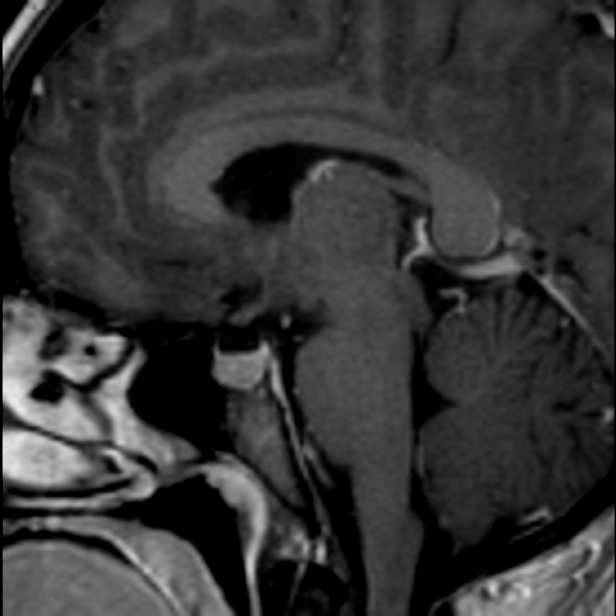

Clásicamente se describe como una alteración en la producción, circulación o drenaje del líquido cefalorraquídeo. Existen múltiples causas que pueden originar este fenómeno y deben ser ágilmente identificados para su oportuno tratamiento ya que puede poner el riesgo la salud y la vida.

El tratamiento es inminentemente quirúrgico, a través de la colocación de un sistéma de derivación o utilizando técnicas endoscópicas.